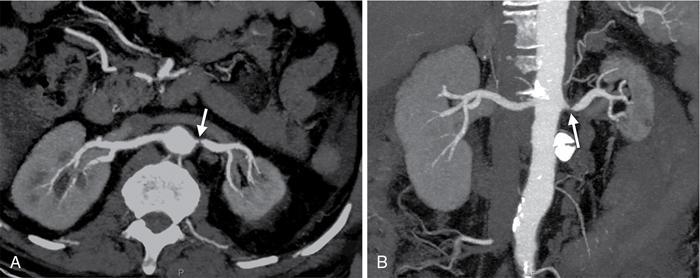

• CTA: CTA helps in delineating the location and extent of thrombus. Superior extent of thrombus into IVC should always be assessed. CT findings include:

• Nonenhancing filling defect in renal vein with luminal expansion in acute thrombosis (Fig. 10.18.1.8A and B).

• Bulky kidney with perinephric and renal sinus oedema, representing venous congestion.

• Delayed parenchymal enhancement.

• Multiple venous collaterals are seen, in case of chronic thrombosis.

Fig. 10.18.1.8 (A) A case of left renal vein thrombosis as hypodense filling defect (arrows) in left renal vein causing total occlusion. (B) Another case of left renal vein thrombosis (block arrow) is also shown. Also note thrombosis of segmental renal vein (arrowhead).

• CTA: CTA helps in identifying the primary renal neoplasm and the extent of thrombus. CT findings include:

• Heterogeneously enhancing filling defect in renal vein with luminal expansion and having continuity with the renal mass (Fig. 10.18.1.9).

• Heterogeneously enhancing renal mass.

• Multiple venous collaterals are seen, in case of subacute to chronic tumour thrombosis.

• Renal vein leiomyosarcoma will appear as heterogeneously enhancing filling defect in the renal vein with or without renal parenchymal involvement. The intravascular component of the tumour is larger as compared to intrarenal component, which helps in differentiating it from primary renal cell carcinoma with tumour thrombus in renal vein.

Fig. 10.18.1.9 (A) Axial and (B) coronal CT images of right kidney showing heterogeneously enhancing mass lesion infiltrating renal vein (arrows) and extending into the IVC, suggesting tumour thrombosis. Also note nonenhancing thrombus in the IVC (arrowhead).